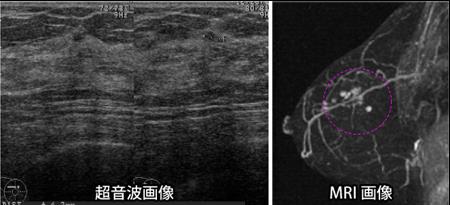

中国患者赴日本治疗乳腺癌病例

某女士 年龄:45 住址:大连

病例:乳腺癌中期

治疗:乳房切除修复再造手术

2011年9月份在中国检查身体,没有发现异常。2012年初,参加东洋医疗的健康之旅。在日本进行健康体检时发现乳腺癌,并判定为癌症初期,当地医院专家给予立即手术的建议。该女士将日本的检查报告带回国内,到北京、大连等医院进行复查,国内医生根据癌细胞的增长情况给予全部切除的建议。最后,该女士决定到日本进行我方推荐的乳房切除修复再造手术。2012年1月,该女士在日本冈山医科大学医院进行了13小时的乳房切除修复再造手术。该手术特点:刀口小、病变清除干净、乳房修复部分采用自身腹部脂肪,不存在任何排斥现象。修复后的乳房左右对称,不影响正常生活。2012年6月,该女士到日本进行第三次复查,术后状况非常好。患者本人也非常满意。